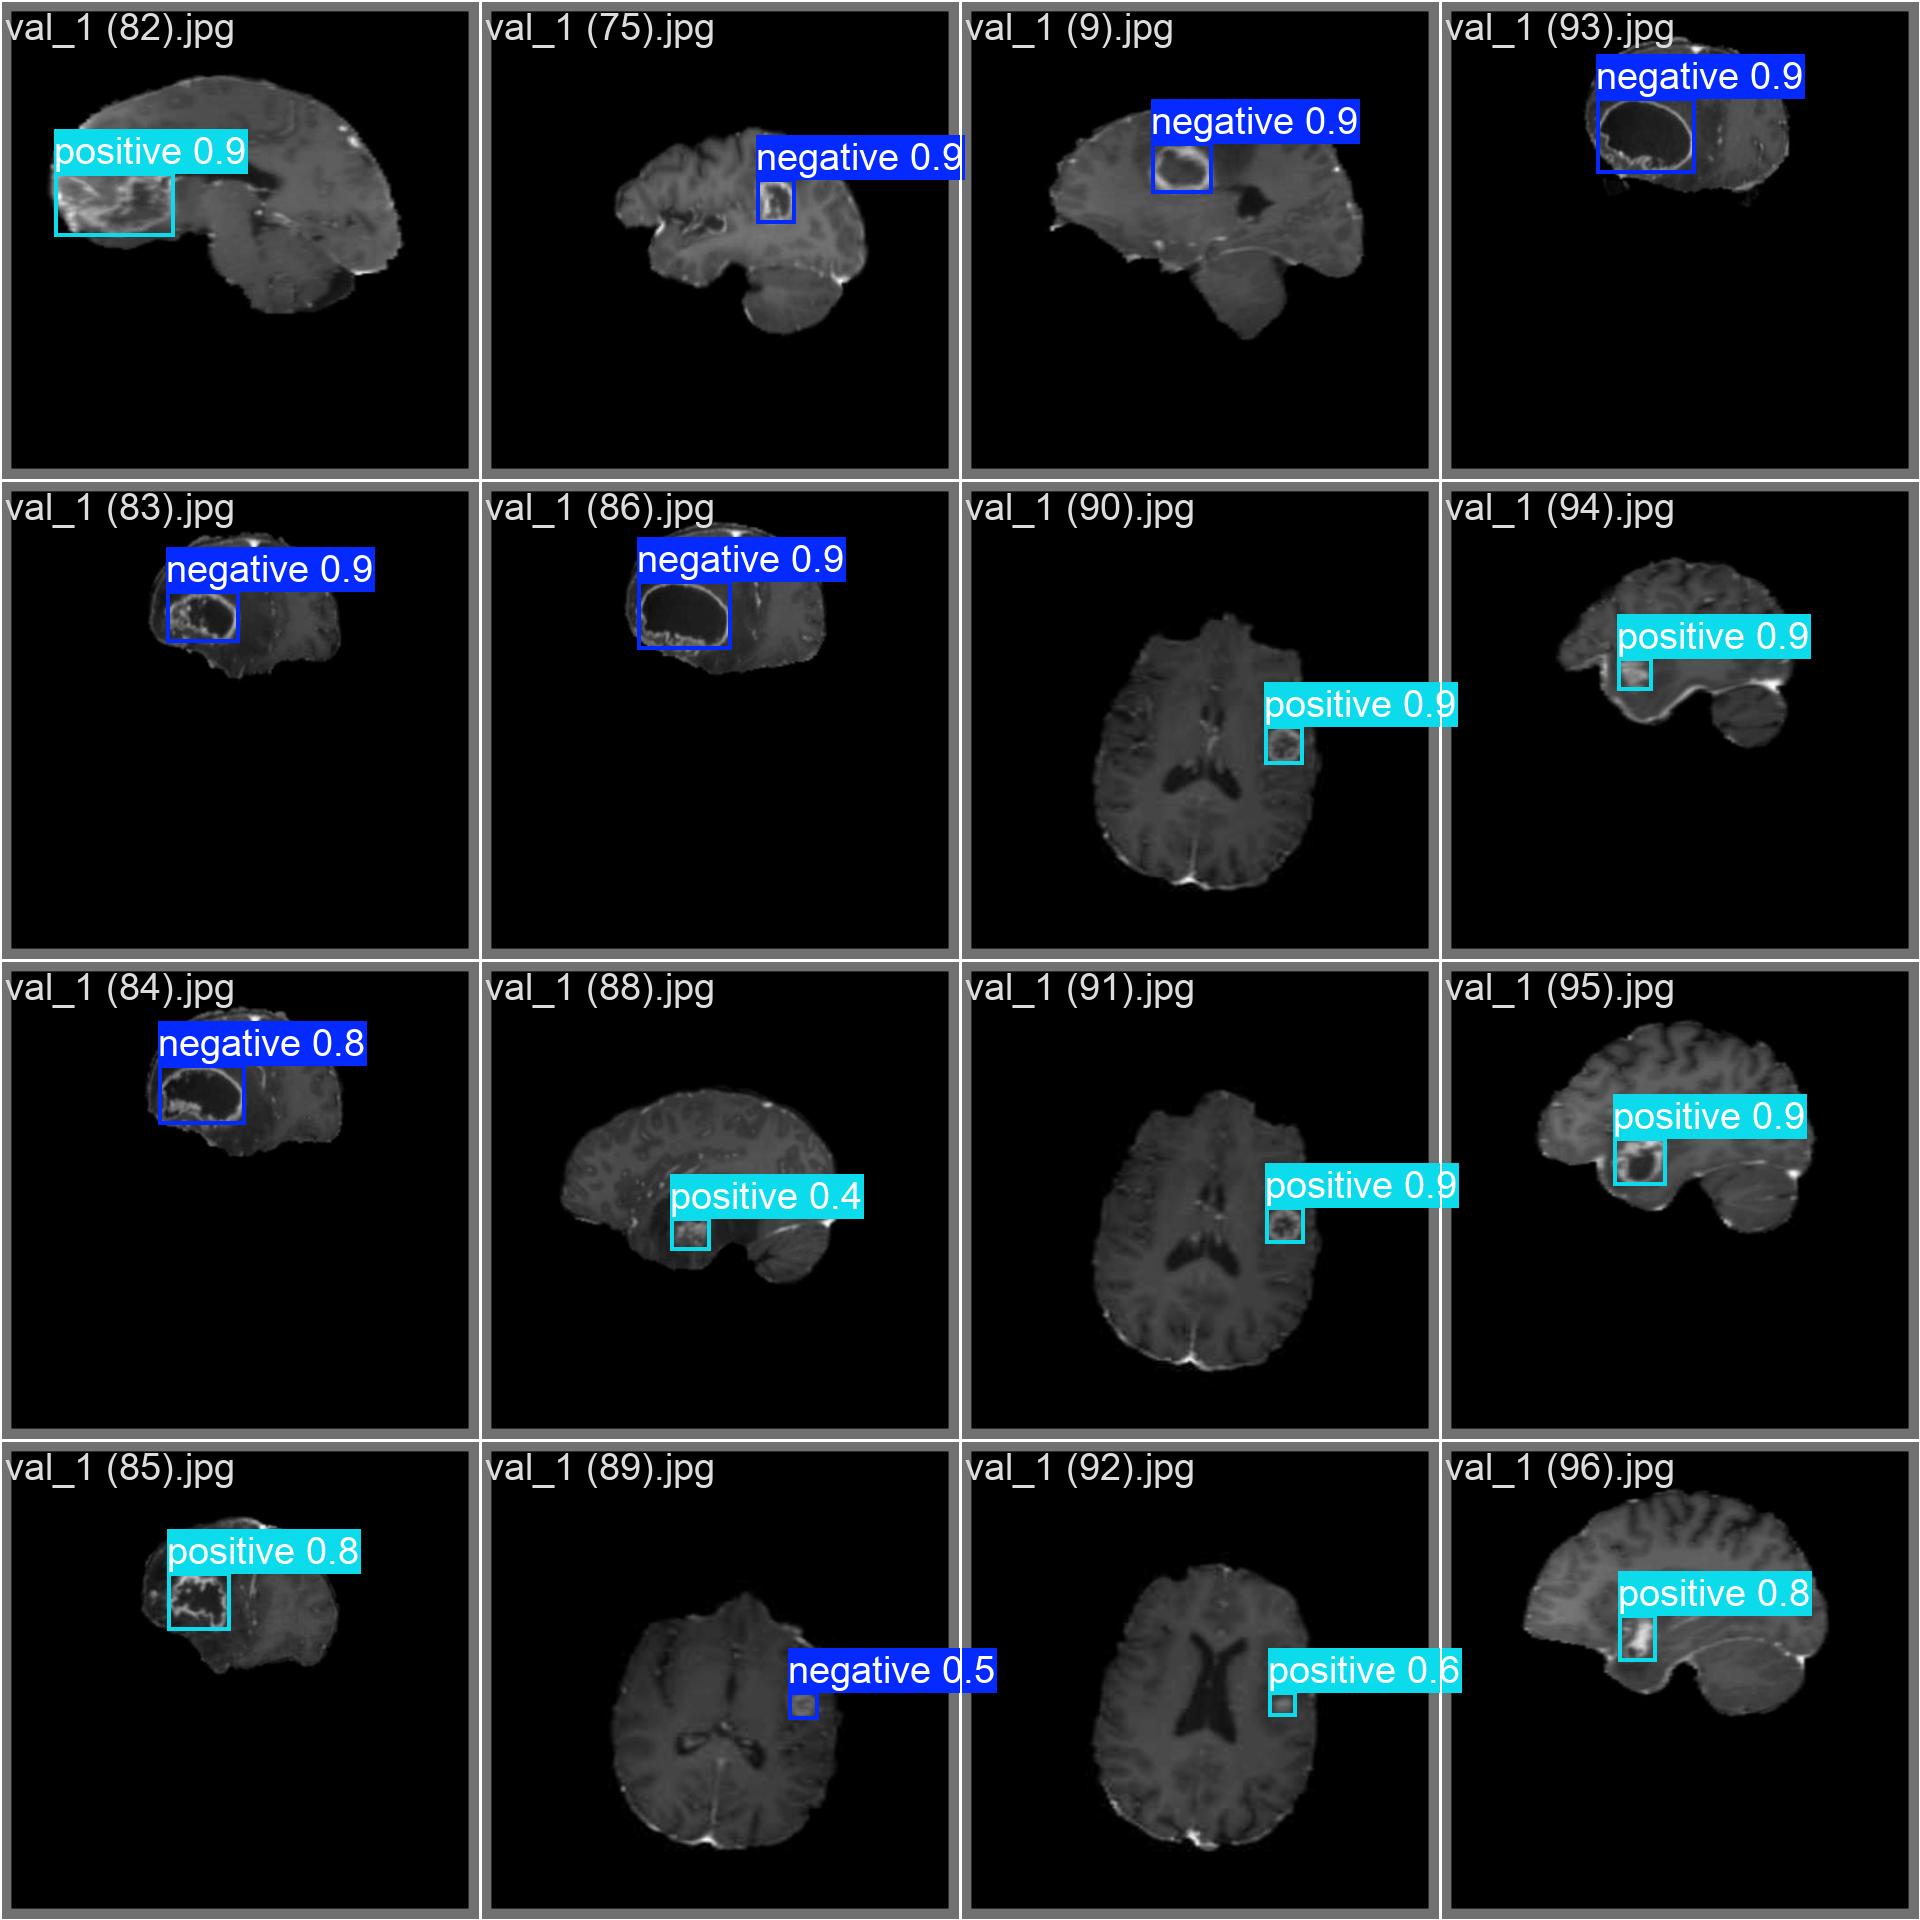

negative:表示图像中存在阴性肿瘤(如良性、低级别或无活性病灶)positive:表示图像中存在阳性肿瘤(如恶性、高级别或活跃增殖病灶)

⚠️ 注:此处"阴性/阳性"指肿瘤的生物学行为或临床意义,具体定义需依据标注规范。

6. 结果与分析

- 精度 : 通过测试集评估模型的 mAP@0.5 等指标,YOLOv12 在高质量标注数据上通常能达到较高精度。

- 速度: YOLOv12 推理速度快,能满足单帧 MRI 图像的实时检测需求。

- 鲁棒性: 模型对不同 MRI 模态、噪声、部分遮挡具有一定鲁棒性。

挑战:

- 小目标检测: 早期微小肿瘤在图像中占比极小。

- 类别混淆: 阴性与阳性肿瘤在影像上可能外观高度相似。

- 边界模糊: 肿瘤浸润性生长导致边缘不清。

本文详细介绍了基于 YOLOv12 和 OpenCV 实现脑肿瘤检测的完整流程。通过定义 negative 和 positive 两类目标,我们构建了一个既能定位又能初步判别肿瘤性质的智能系统。该技术在医学影像辅助诊断、大规模筛查、手术规划等领域具有广阔的应用前景。